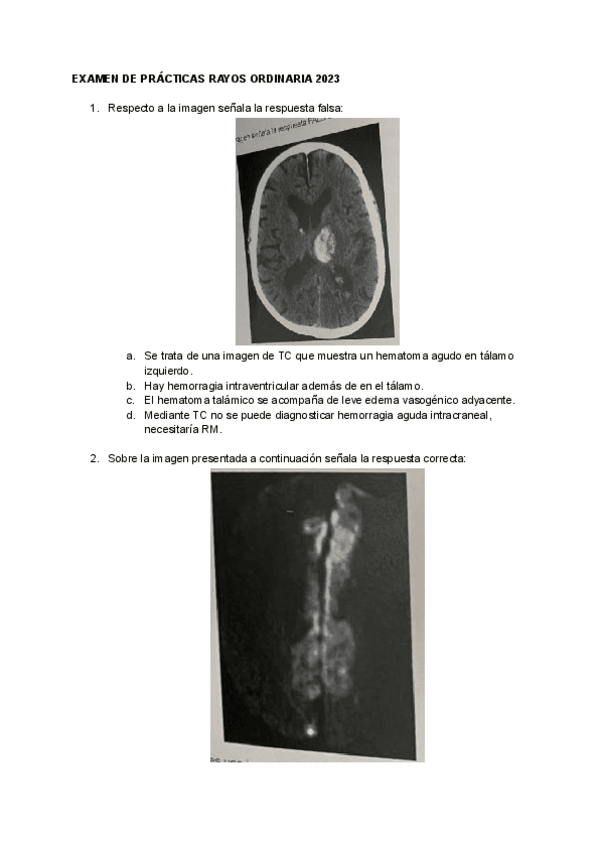

PRÁCTICAS RAYOS X 2023